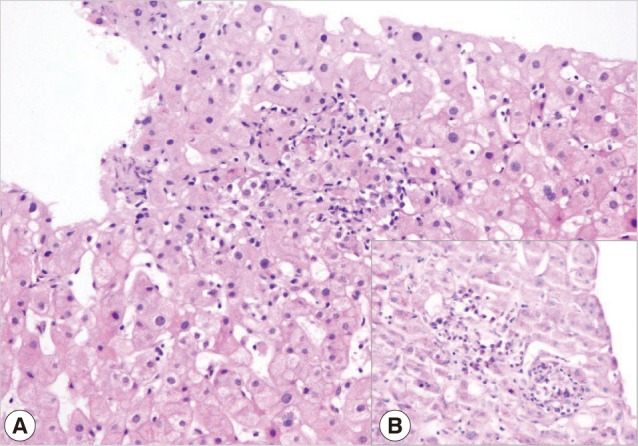

Visceral Leishmaniasis Mimicking Autoimmune Hepatitis, Primary Biliary Cirrhosis, and Systemic Lupus Erythematosus Overlap

The Korean Journal of Parasitology 2012;50(2):133-136.